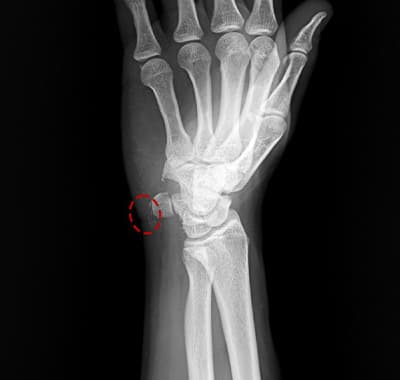

X-ray, 초음파, MRI로 석회의 위치, 크기, 경도 확인. 석회 단계(형성기/휴지기/흡수기) 판단.